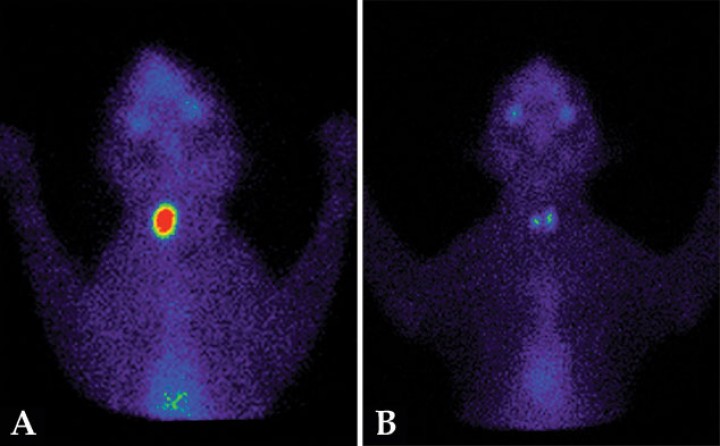

Aproximadamente un 30 % de los gatos hipertiroideos presentan un aumento de tamaño y una mayor captación del radiofármaco en un solo lóbulo tiroideo (patrón unilateral) (Fig. 2A).[ Xifra MP, Peterson ME. Hipertiroidismo felino. En: Pérez MD, Arenas C, Melian C (eds): Manual de Endocrinología en Pequeños Animales. 2ª ed. Barcelona, España. Multimédica; 2018:143-192. , Peterson ME, Broome MR. Thyroid scintigraphy findings in 2096 cats with hyperthyroidism. Vet Radiol Ultrasound. 2015; 56(1):84-95. [PubMed] ] El lóbulo contralateral normal no será visible al tener su funcionalidad disminuida y no captar pertecnetato, ya que el lóbulo hiperfuncional suprime la secreción de tirotropina (TSH).[ Xifra MP, Peterson ME. Hipertiroidismo felino. En: Pérez MD, Arenas C, Melian C (eds): Manual de Endocrinología en Pequeños Animales. 2ª ed. Barcelona, España. Multimédica; 2018:143-192. ] Si el lóbulo contralateral presenta captación del radiofármaco, aunque la ratio T/S no esté aumentada, se considera que su tejido es hiperfuncional y, por lo tanto, se clasifica como patrón bilateral (Fig. 2B).[ Xifra MP, Peterson ME. Hipertiroidismo felino. En: Pérez MD, Arenas C, Melian C (eds): Manual de Endocrinología en Pequeños Animales. 2ª ed. Barcelona, España. Multimédica; 2018:143-192. , Peterson ME, Broome MR. Thyroid scintigraphy findings in 2096 cats with hyperthyroidism. Vet Radiol Ultrasound. 2015; 56(1):84-95. [PubMed] ]

<p>Gammagrafías tiroideas con diferentes patrones de lesión en gatos. (<strong>A</strong>) Gato hipertiroideo, patrón unilateral. Aumento de captación de <sup>99m</sup>Tc (ratio T/S: 4,8) en el lóbulo tiroideo izquierdo. Lóbulo derecho suprimido y no visible. (<strong>B</strong>) Gato hipertiroideo, patrón bilateral. Aumento de captación (ratio T/S: 2,7) en el lóbulo tiroideo izquierdo. El lóbulo derecho es visible, y aunque su captación tenga una ratio T/S<1,5 (=1,06), se considera hiperfuncional. (<strong>C</strong>) Gato hipertiroideo, patrón bilateral asimétrico. Aumento de captación (ratio T/S: 6,35) en ambos lóbulos. El lóbulo tiroideo izquierdo, de mayor tamaño, aparece desplazado a la entrada de la cavidad torácica. (<strong>D</strong>) Gato hipertiroideo, patrón multifocal con tejido ectópico. Aumento de captación (ratio T/S: 14,4) en los dos lóbulos tiroideos y en tejido tiroideo ectópico mediastínico.</p>

Gammagrafías tiroideas con diferentes patrones de lesión en gatos. (A) Gato hipertiroideo, patrón unilateral. Aumento de captación de 99mTc (ratio T/S: 4,8) en el lóbulo tiroideo izquierdo. Lóbulo derecho suprimido y no visible. (B) Gato hipertiroideo, patrón bilateral. Aumento de captación (ratio T/S: 2,7) en el lóbulo tiroideo izquierdo. El lóbulo derecho es visible, y aunque su captación tenga una ratio T/S<1,5 (=1,06), se considera hiperfuncional. (C) Gato hipertiroideo, patrón bilateral asimétrico. Aumento de captación (ratio T/S: 6,35) en ambos lóbulos. El lóbulo tiroideo izquierdo, de mayor tamaño, aparece desplazado a la entrada de la cavidad torácica. (D) Gato hipertiroideo, patrón multifocal con tejido ectópico. Aumento de captación (ratio T/S: 14,4) en los dos lóbulos tiroideos y en tejido tiroideo ectópico mediastínico.

El 70 % de los gatos hipertiroideos presentan un patrón bilateral con afectación de ambos lóbulos (Fig. 2C).[ Xifra MP, Peterson ME. Hipertiroidismo felino. En: Pérez MD, Arenas C, Melian C (eds): Manual de Endocrinología en Pequeños Animales. 2ª ed. Barcelona, España. Multimédica; 2018:143-192. , Peterson ME, Broome MR. Thyroid scintigraphy findings in 2096 cats with hyperthyroidism. Vet Radiol Ultrasound. 2015; 56(1):84-95. [PubMed] ] En estos casos el aumento de tamaño y captación puede ser simétrico o asimétrico.

En un pequeño número de gatos, el hipertiroidismo puede estar producido por lesiones multifocales (más de dos áreas de captación del radionucleótido).[ Xifra MP, Peterson ME. Hipertiroidismo felino. En: Pérez MD, Arenas C, Melian C (eds): Manual de Endocrinología en Pequeños Animales. 2ª ed. Barcelona, España. Multimédica; 2018:143-192. , Peterson ME, Broome MR. Thyroid scintigraphy findings in 2096 cats with hyperthyroidism. Vet Radiol Ultrasound. 2015; 56(1):84-95. [PubMed] ] Como la gammagrafía tiroidea evidencia todo el tejido tiroideo existente, es muy útil para detectar lesiones en cualquier localización. Un pequeño porcentaje de gatos (<4 %) presenta tejido tiroideo ectópico, localizado desde el área sublingual hasta el mediastino craneal, que puede aparecer hiperfuncional en casos de hipertiroidismo (Fig. 2D). También permite visualizar lóbulos tiroideos hiperfuncionales desplazados a la cavidad torácica, ya que la glándula tiroidea está poco adherida a los tejidos adyacentes y, al hipertrofiarse, aumenta de peso y puede introducirse en la cavidad torácica.[ Xifra MP, Peterson ME. Hipertiroidismo felino. En: Pérez MD, Arenas C, Melian C (eds): Manual de Endocrinología en Pequeños Animales. 2ª ed. Barcelona, España. Multimédica; 2018:143-192. , Peterson ME, Broome MR. Thyroid scintigraphy findings in 2096 cats with hyperthyroidism. Vet Radiol Ultrasound. 2015; 56(1):84-95. [PubMed] ]